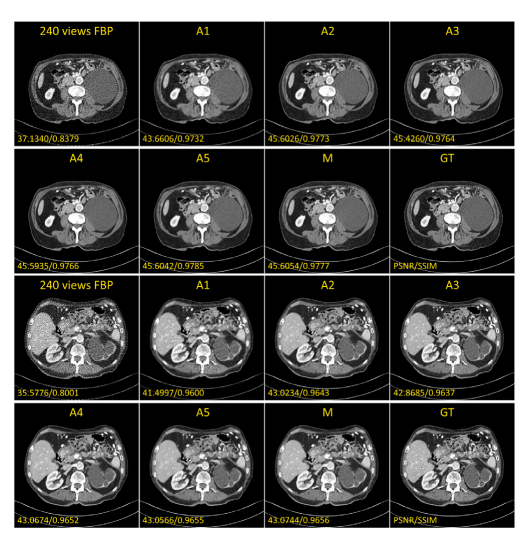

Fig. 7. The prediction results of different ablation models (together with quantitativeresults of PSNR and SSIM). The set range of the display window is a window levelof 40 HU and a window width of 400 HU (i.e., a range from −160 HU to 240 HU).A1: Learn mapping in the projection domain, directly reconstruct CT with FBP, noimage domain optimization. A2: Mapping learned only in the image domain. Inputis FBP-reconstructed image from noisy sparse-view sinograms 𝑆𝑖 . A3: Main networkbut without forward projection feedback loss and bicubic interpolation loss. A4: Mainnetwork with enhanced pixel-level L2 loss. A5: Main network but without perceptualloss. M: Our full model.

图7. 不同消融模型的预测结果(包括PSNR和SSIM的定量结果)。显示窗口的设置范围为窗位40 HU,窗宽400 HU(即范围为−160 HU到240 HU)。A1:仅在投影域中学习映射,直接通过FBP重建CT图像,无图像域优化。A2:仅在图像域中学习映射,输入为从噪声稀疏视角正弦图 𝑆𝑖 通过FBP重建的图像。A3:主网络,但没有前向投影反馈损失和双三次插值损失。A4:主网络,增强了像素级的L2损失。A5:主网络,但没有感知损失。M:我们的完整模型。